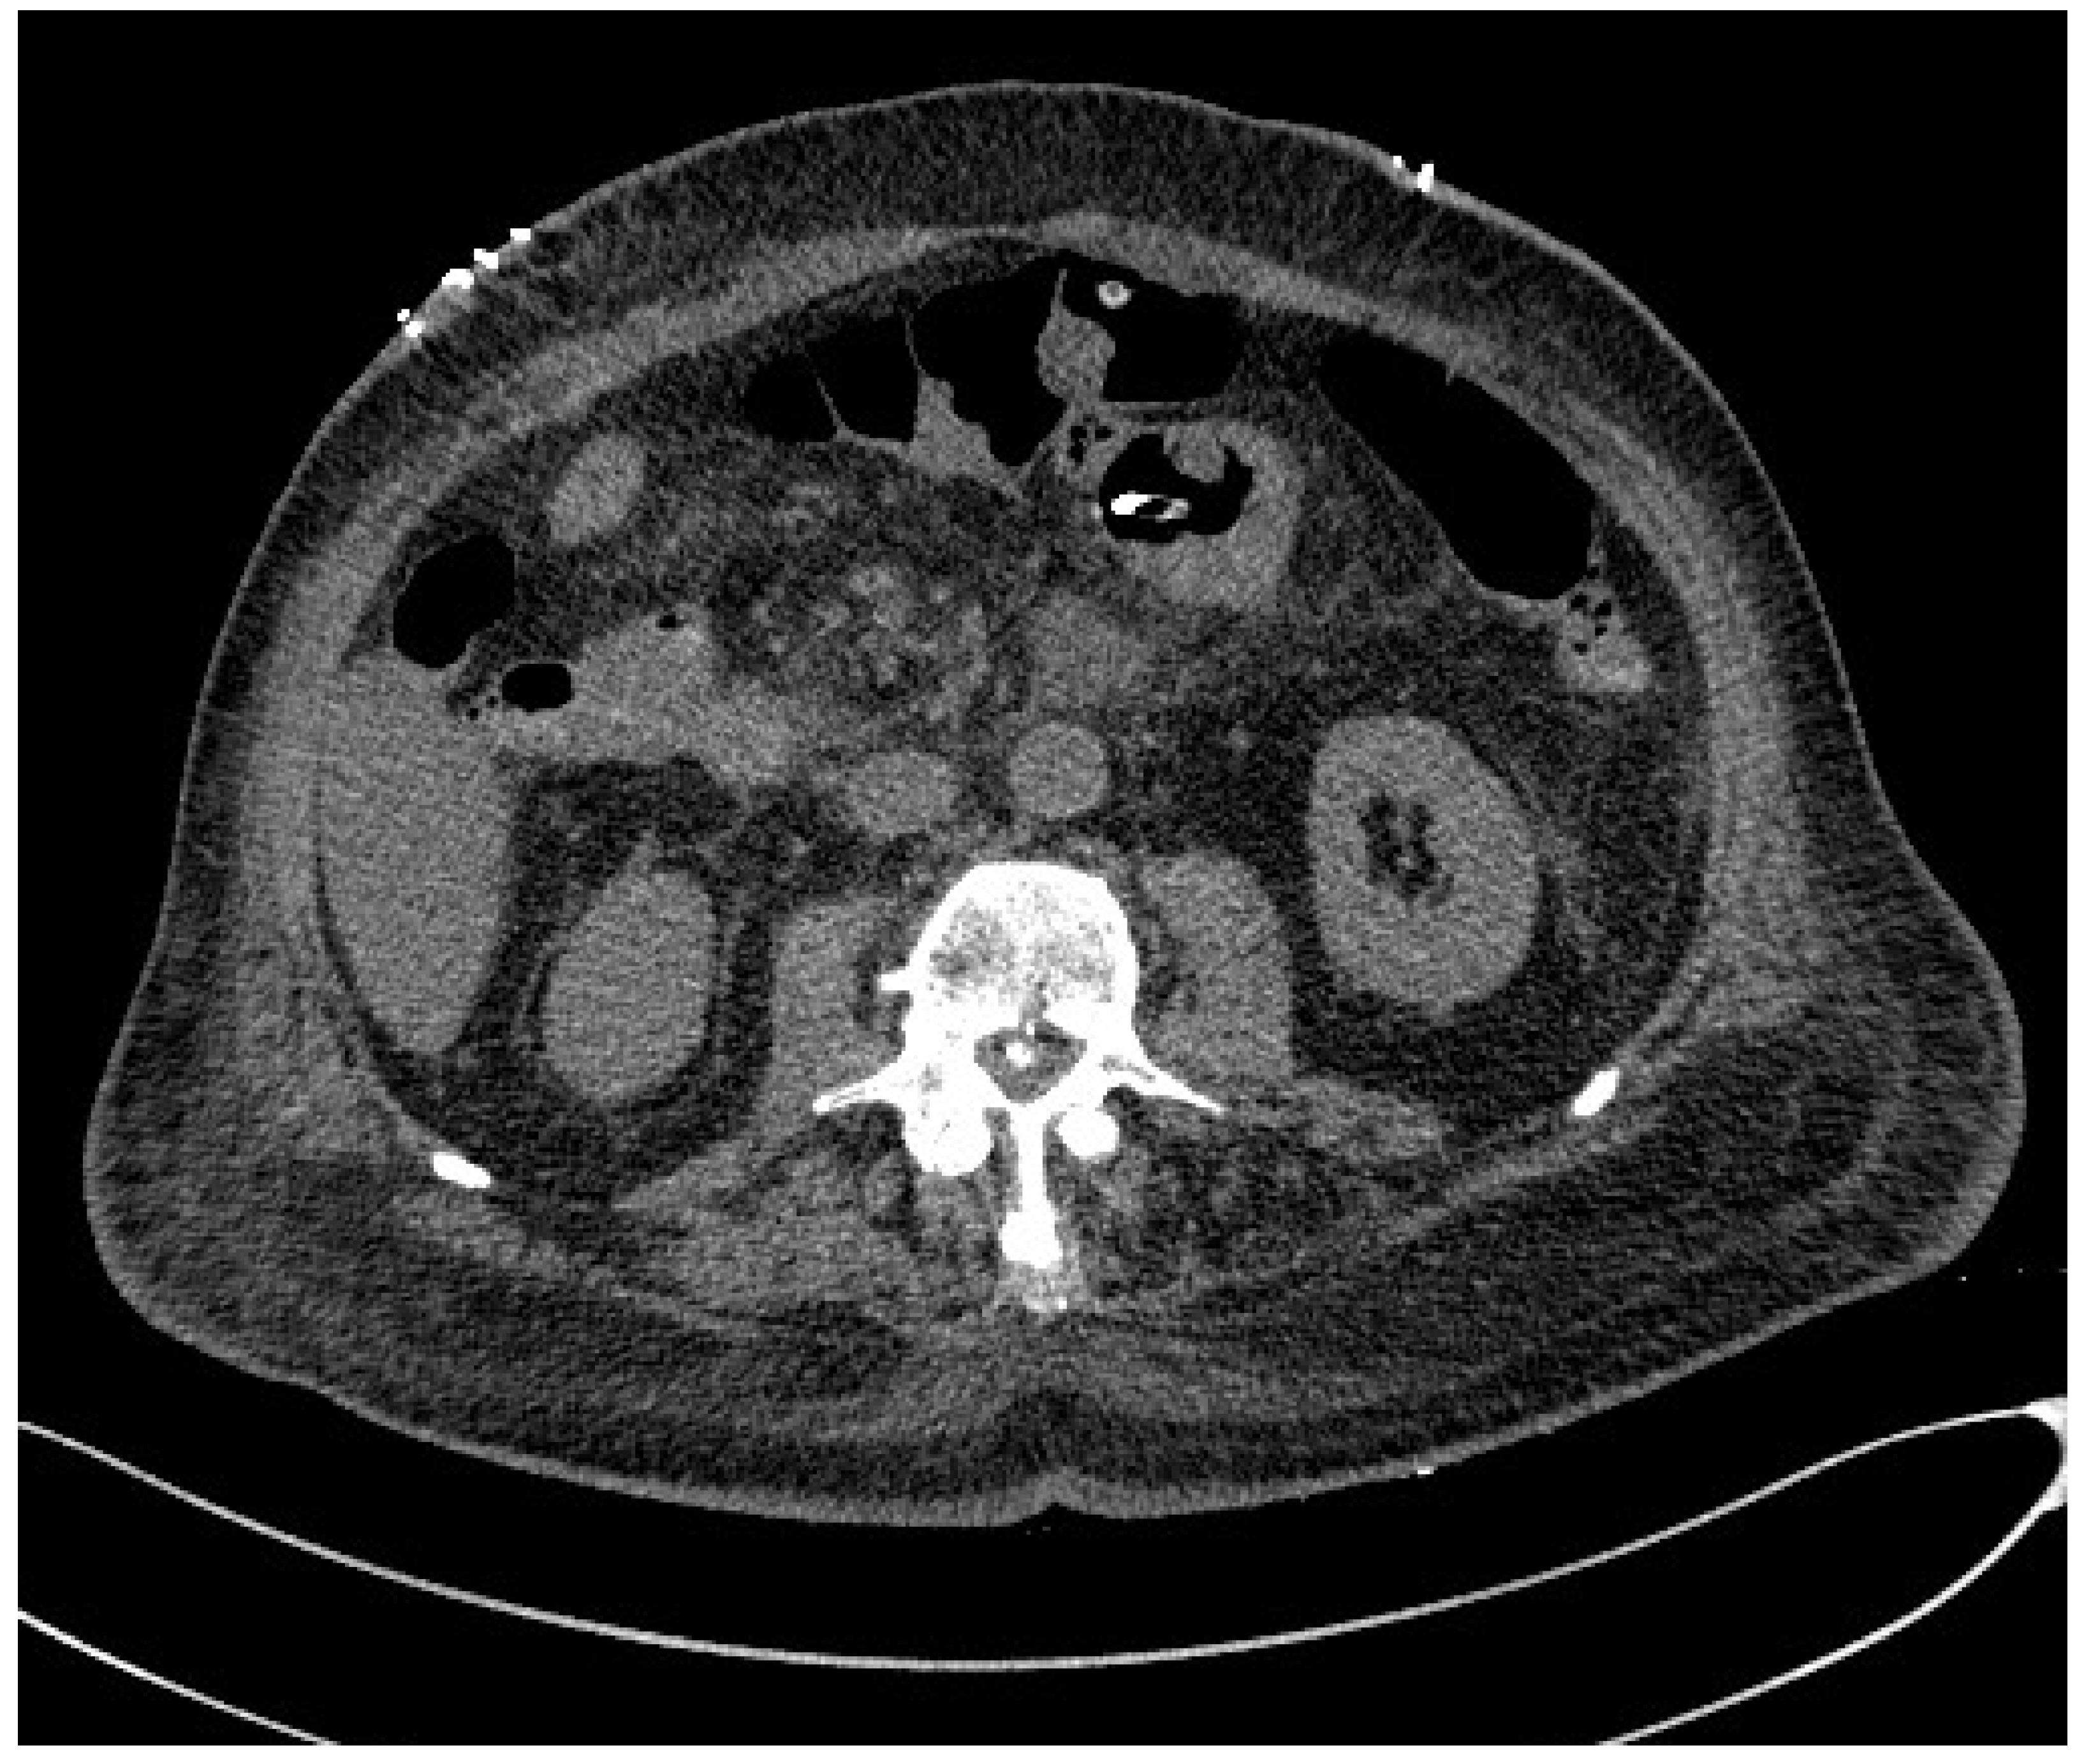

3.1. Computed Tomography

- Albano, D.; Messina, C.; Vitale, J.; Sconfienza, L.M. Imaging of sarcopenia: Old evidence and new insights. Eur. Radiol. 2020, 30, 2199–2208. [Google Scholar] [CrossRef]